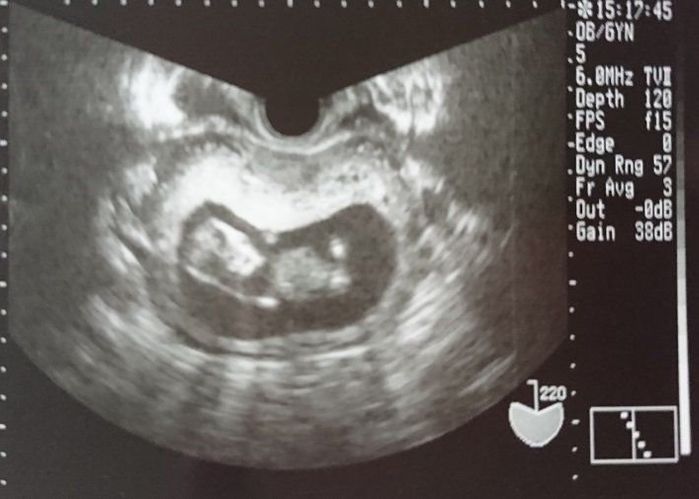

妊娠7週目のエコー写真 赤ちゃんの心臓の鼓動が聞こえた!

年を越して、約2週間ぶりに健診に行きましたが、とても待ち遠しかったです。

前回はエコー画像だけだったので、実感はあまりありませんでしたが、今回は赤ちゃんの心臓の鼓動を聞く事ができたので、とても感動しました。まだ赤ちゃんの袋の大きさは“小豆粒”くらいだそうですが、立派に生きている鼓動が聞けて嬉しかったです。母子手帳をもらいに行きました。